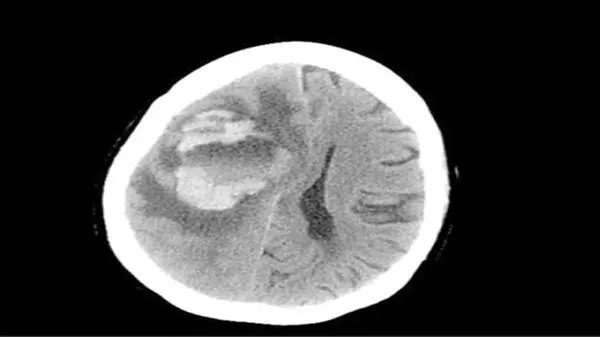

پزشکان بیمارستانی در آمریکا پس از کالبدشکافی متوجه شدند گونهای از یک آمیب (جاندار تکیاختهای) نادر از طریق آب وارد مغز او شده و بخشی از آنرا خورده است. پزشکان در مصاحبه با سایت دیلیمیل، استفاده از آب لولهکشی بهجای محلول شستوشوی سینوس را عامل این مرگ اعلام کردند.اخبار 24 ساعت گذشته رکنا را از دست ندهید